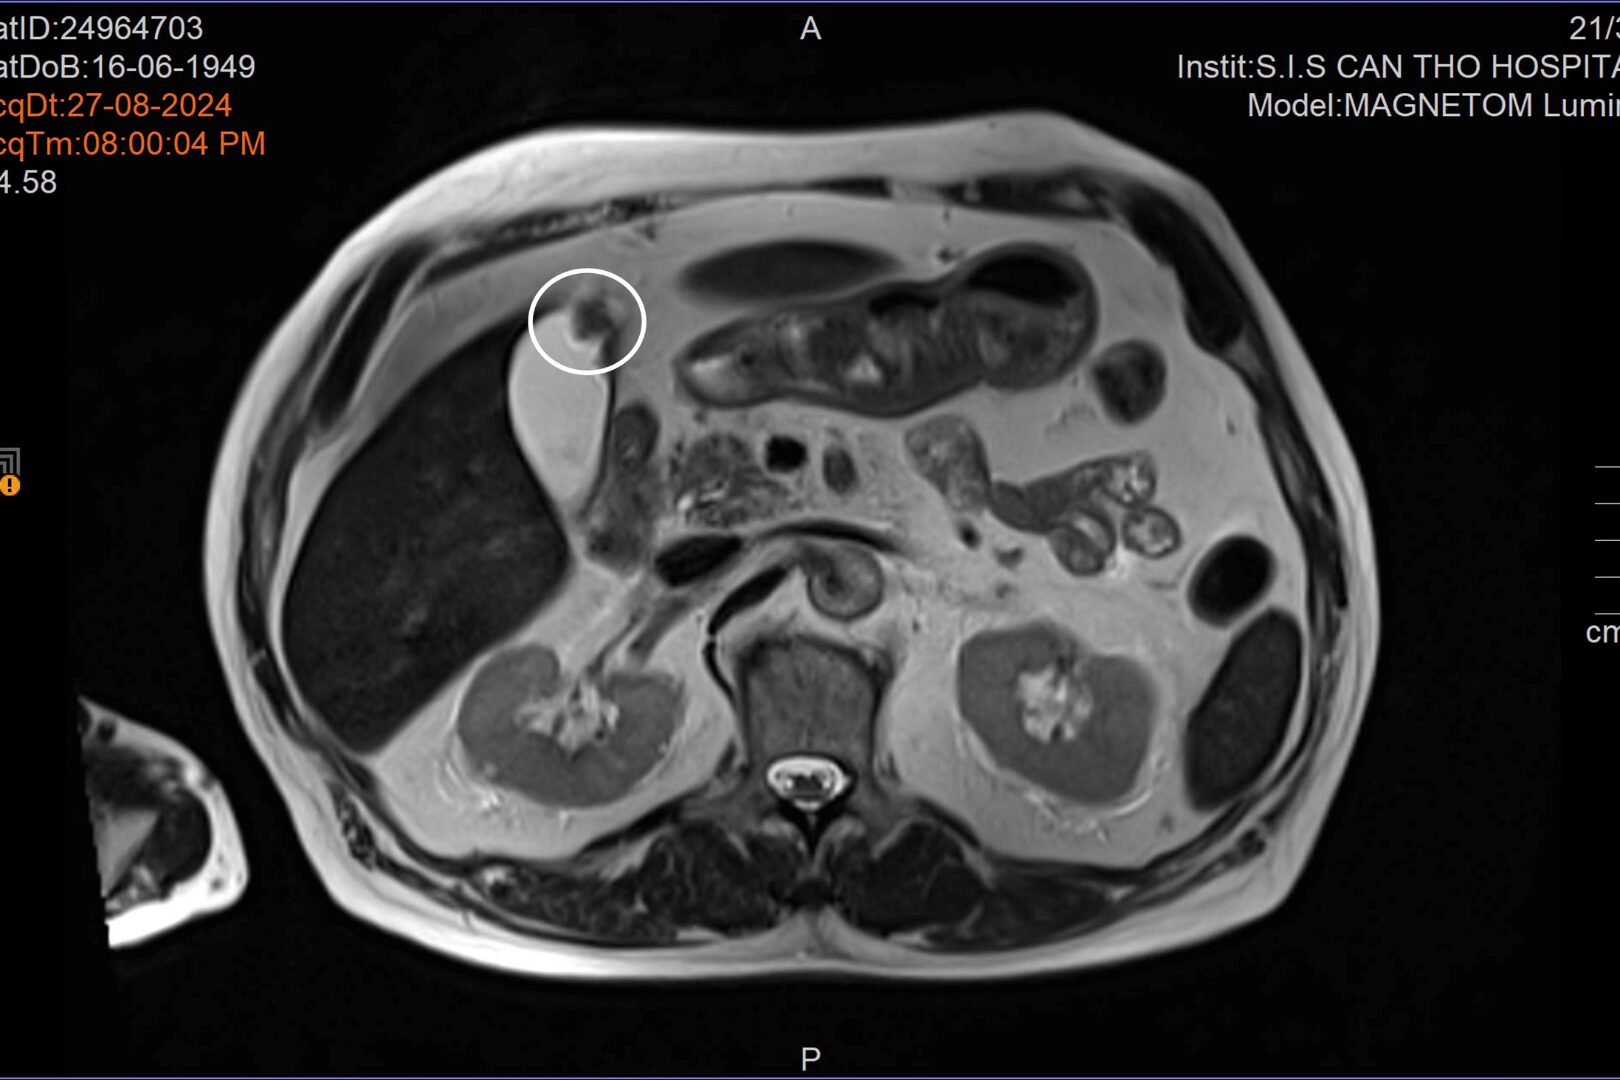

U gan (ảnh trên) và u túi mật được phát hiện khi bệnh nhân đến tái khám tình trạng tai biến (Ảnh: BVCC)

Trong đợt tái khám, kết quả các cận lâm sàng cho thấy bệnh nhân có những tổn thương ở gan và túi mật. ThS.BS Đặng Văn Sô Đa – Khoa Ngoại tổng tợp, Bệnh viện Đa khoa Quốc tế S.I.S Cần Thơ cho biết: “Ung thư túi mật là một bệnh lý hiếm gặp. Bệnh nhân lại cùng lúc có ung thư túi mật và ung thư gan. Bệnh nhân được điều trị bằng phương pháp nội soi ổ bụng, cắt túi mật nội soi và cắt một phần gan trước khối u”.